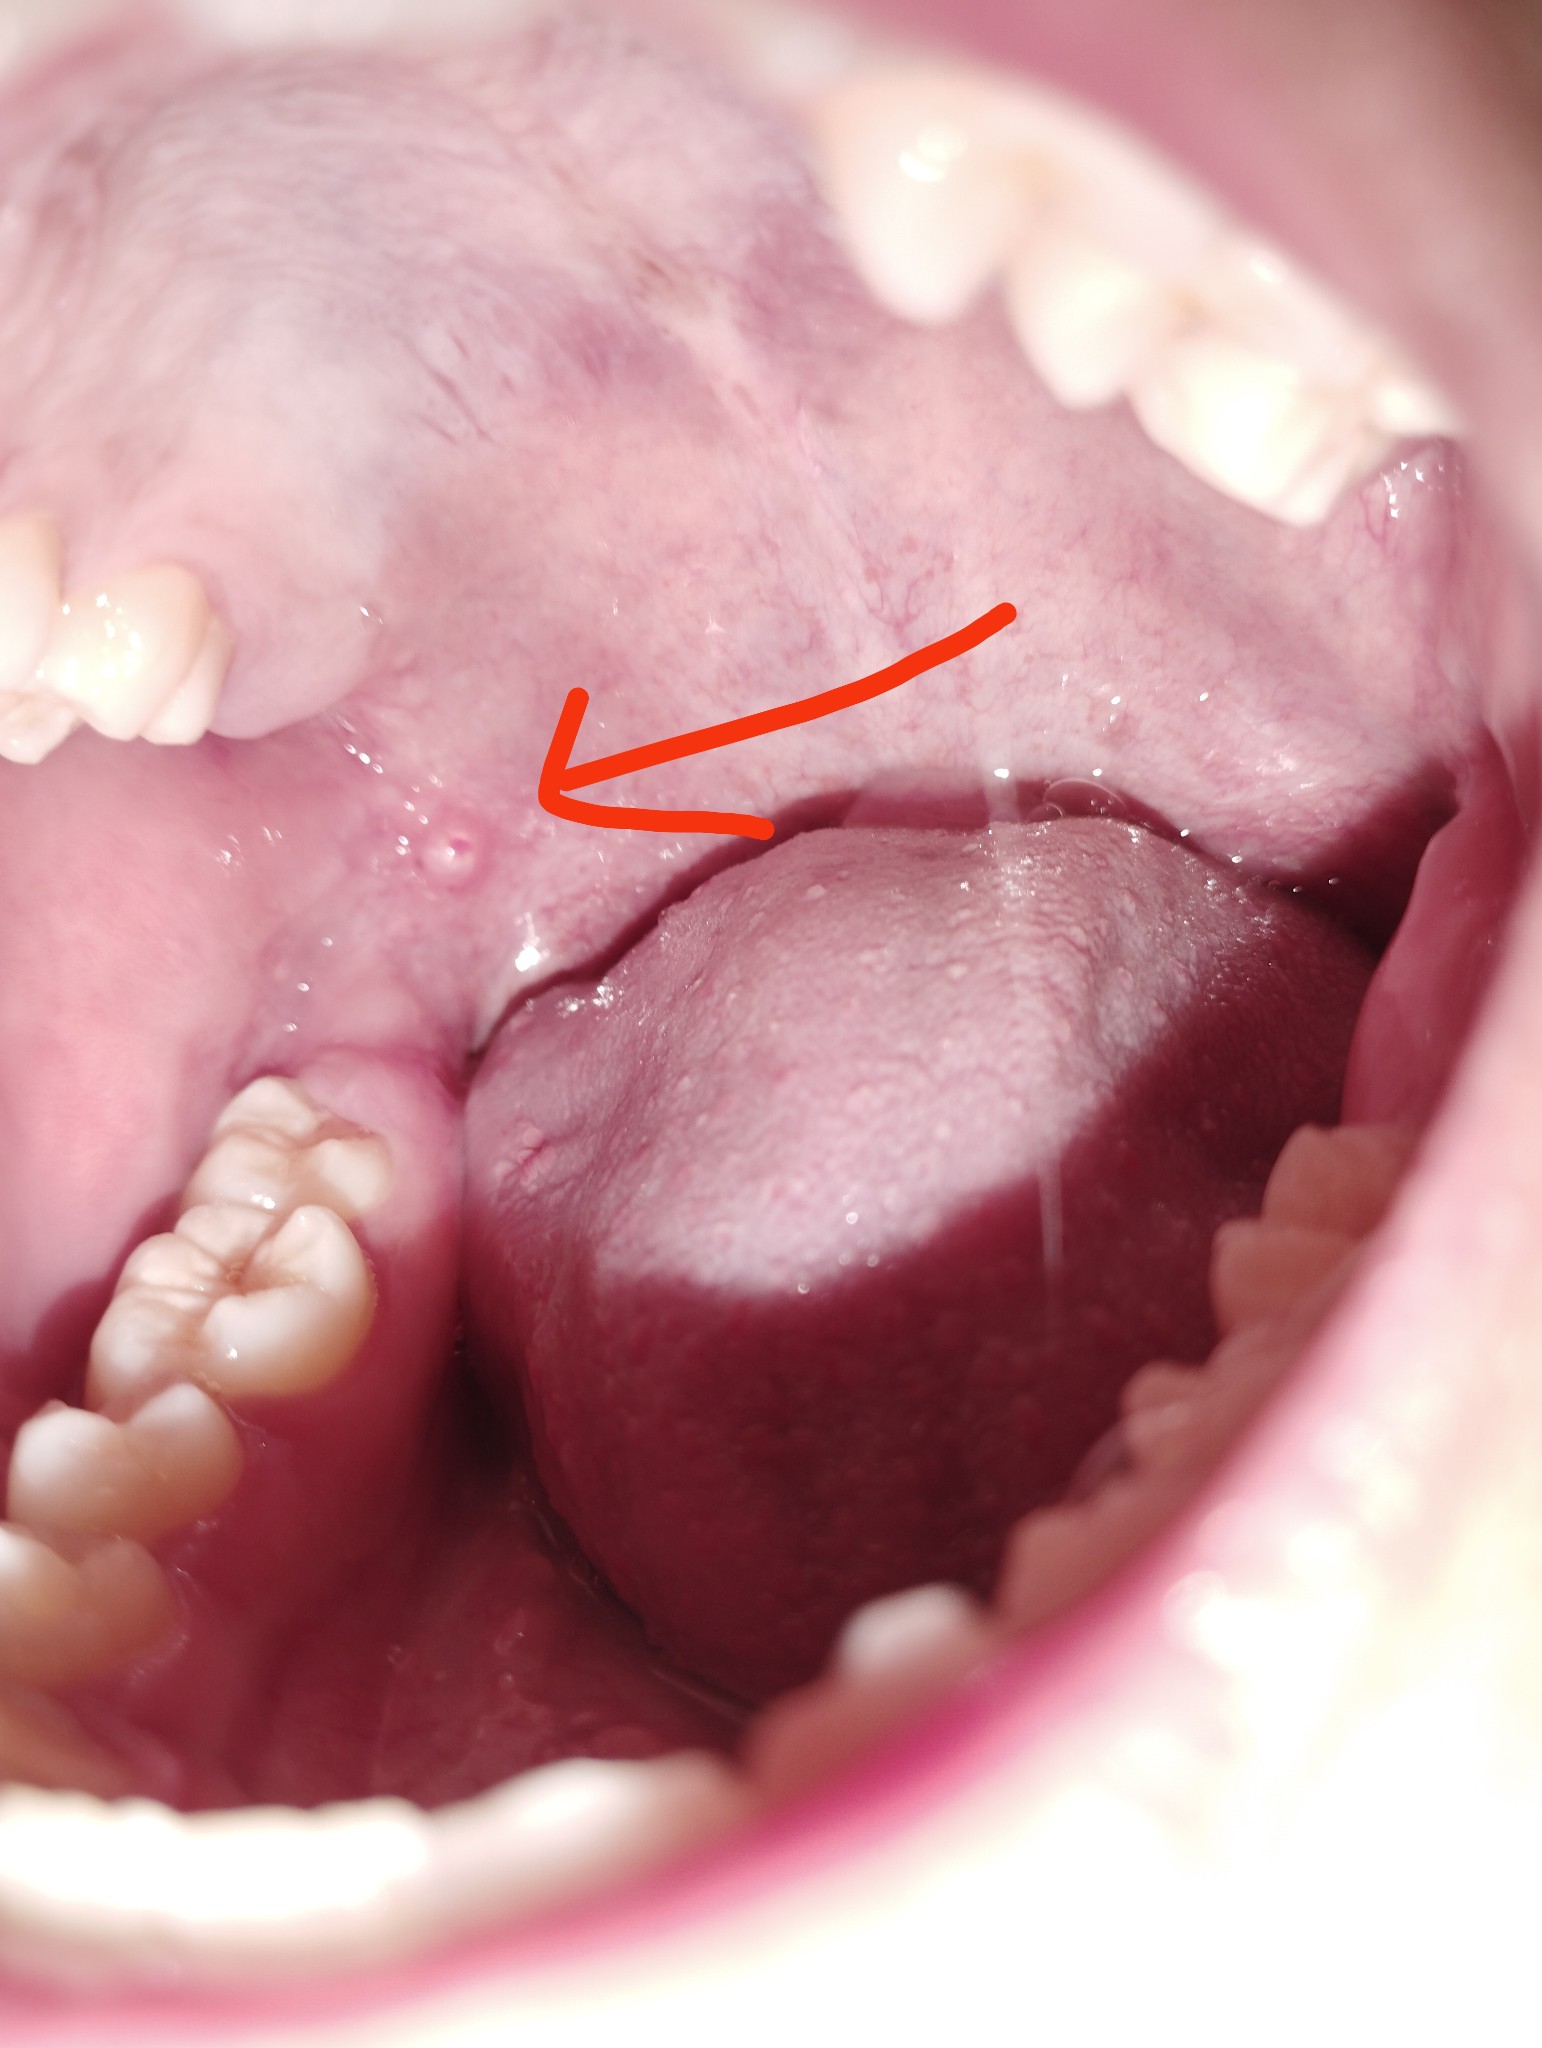

มันคืออะไรหรอครับมันเป็นเหมือนตุ่มวงกลมใสๆนิ่มๆพอลิ้นไปโดนก็ไม่รู้สึกเจ็บ

มันคืออะไรหรอครับมันเป็นเหมือนก้อนวงกลมใสๆนิ่มๆพอลิ้นไปโดนก็ไม่รู้สึกเจ็บ

ตุ่มที่ขึ้นใสๆในปากใช่ มิวโคซีล หรือเปล่าครับ

คือผมเป็นตุ่มใสๆ อยู่ดีดีมันก็บวมขึ้นมาครับในเหงือก แต่ไม่ได้รู้สึกเจ็บคอรู้สึกเคืองๆ เฉยเฉยครับ แต่แปลใจตรงที่ว่ามันขึ้นขึ้นยุบยุบอ่ะ ผมเป็นมา4-5วันละ มันยุบไปแล้วแล้วมันก็กลับมาขึ้นใหม่ ตรงลักษณะที่